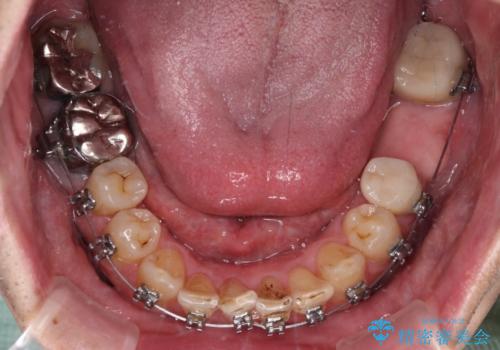

- 近医にてブリッジ治療を行った歯が痛くてたまらないとのことで来院された患者様です。

診察を行ったところ、奥の土台になっている歯は神経組織が失活しており、根尖部に病変があり、そこが原因で痛みを生じている状態でした。

根管治療を行うためにブリッジを除去したところ、むし歯が歯肉の奥深くにあまで及んでいたため、歯周外科処置によりむし歯が歯肉縁より浅い位置へと改善することとしました。

ここまでの治療を提案したところで、折角なのでしっかり治療を行いたいとのことで、前歯のデコボコやクロスバイトを改善するための矯正治療を行うこととしました。

まずは奥歯の痛みを改善し、その後矯正治療を行い、最後にオールセラミックブリッジによる補綴治療を行うこととしました。